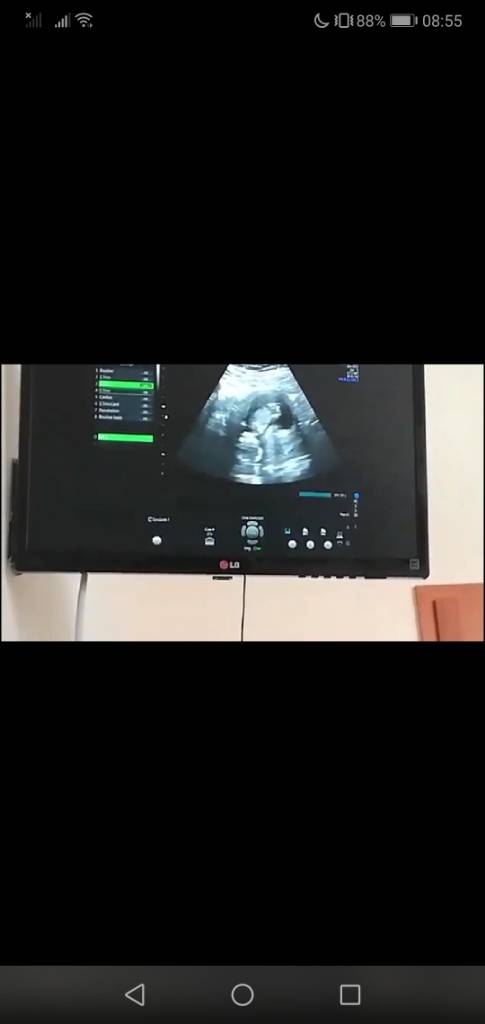

Nie martw się, dzidzia jeszcze wiele razy zmieni pozycję żeby na koniec znów ustawić się głowa do dołu :-)Jest to 14 Tc

1 ciąża to panikę sieje od razuNie martw się, dzidzia jeszcze wiele razy zmieni pozycję żeby na koniec znów ustawić się głowa do dołu :-)